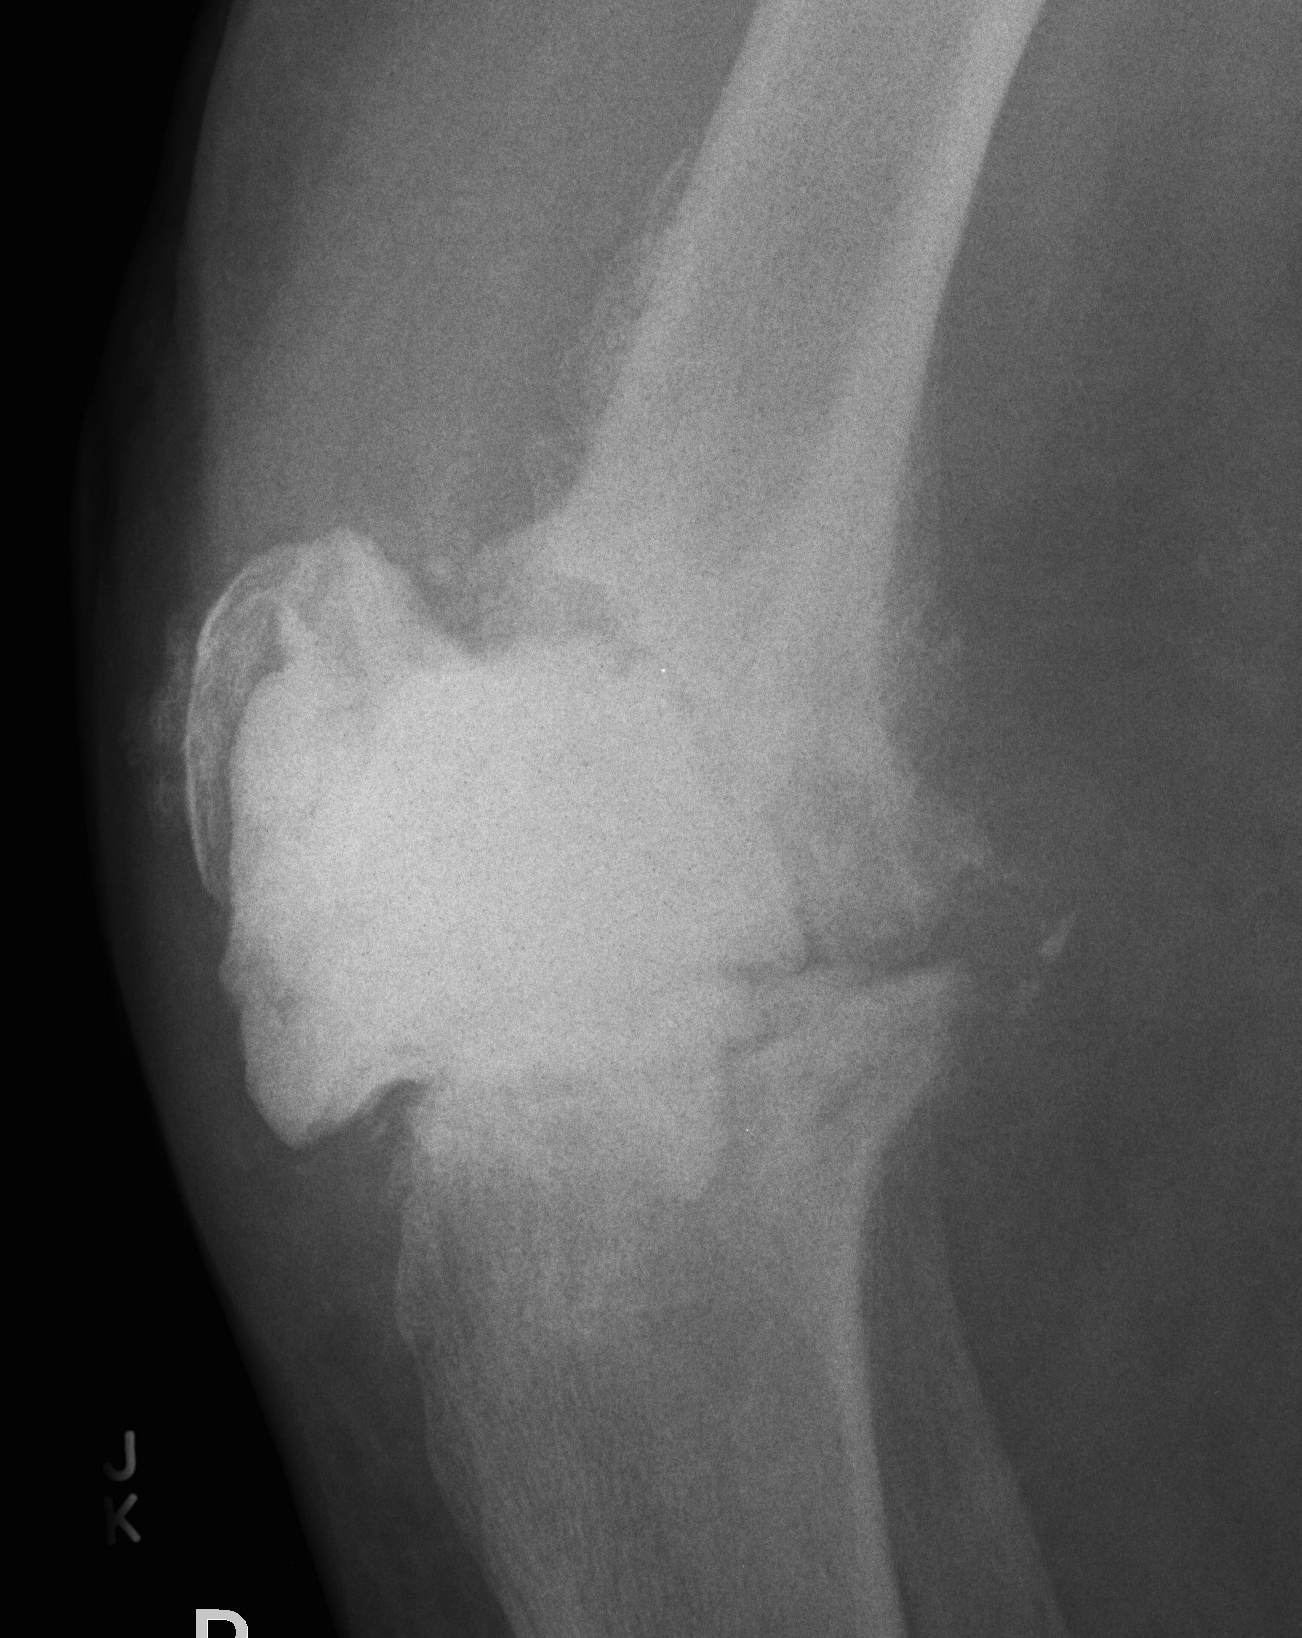

Xray

- progressive early lysis

3. Acute Haematogenous

- antecedent bacteraemia

- can occur several years after surgery

- well patient with previously well functioning knee

- sudden deterioration / swelling / pain

- often have UTI etc